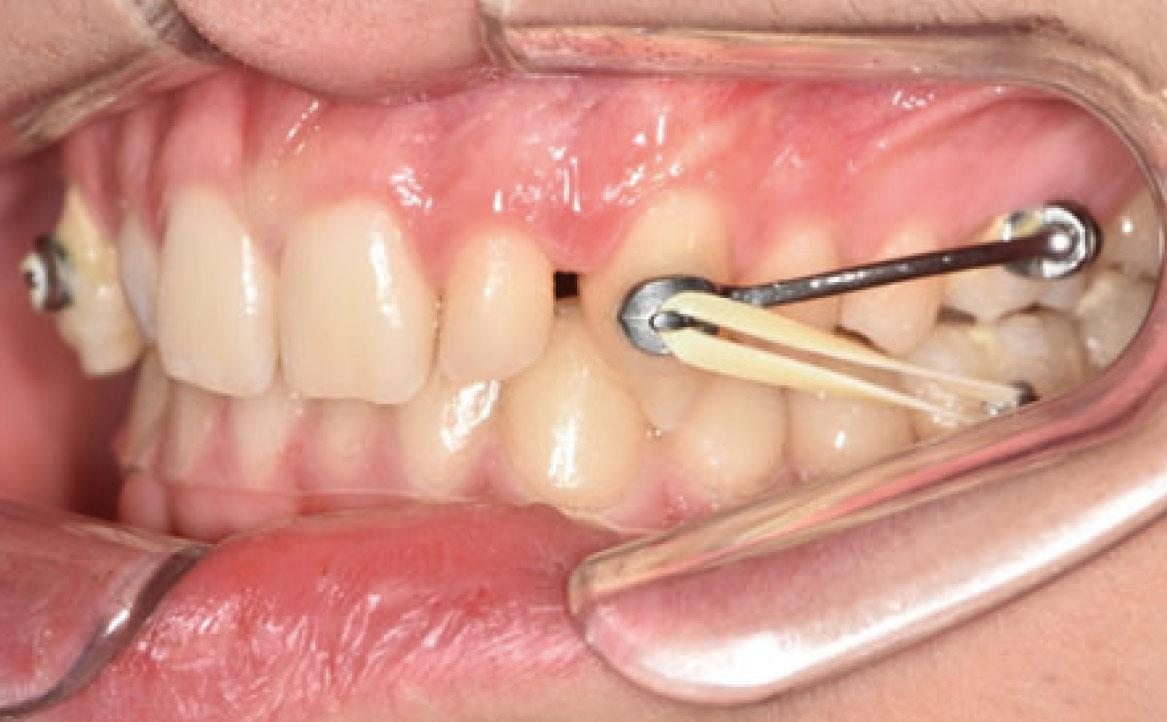

Nello specifico, sono stati eseguiti bandaggi superiori e inferiori con tecnica Damon per l’allineamento e il livellamento delle arcate dentarie con l’aggiunta di rialzi occlusali, al fine di aprire il morso, ed elastici di classe II a tempo pieno (fig. 5a-c).

Dopo circa dieci mesi, è stata eseguita la rimozione dei rialzi occlusali ed è stato ridotto il tempo di utilizzo degli elastici da 24 a 12 ore (solo nelle ore pomeridiane e notturne) (fig. 6a-d). Successivamente, il paziente ha chiesto anche di migliorare l’aspetto estetico degli elementi microdontici 12 e 22. Dopo una discussione con un collega, è stata proposta l’aggiunta di materiali compositi sul lato mesiale e distale di entrambi gli elementi. L’alternativa sarebbe stata l’uso di faccette in composito.